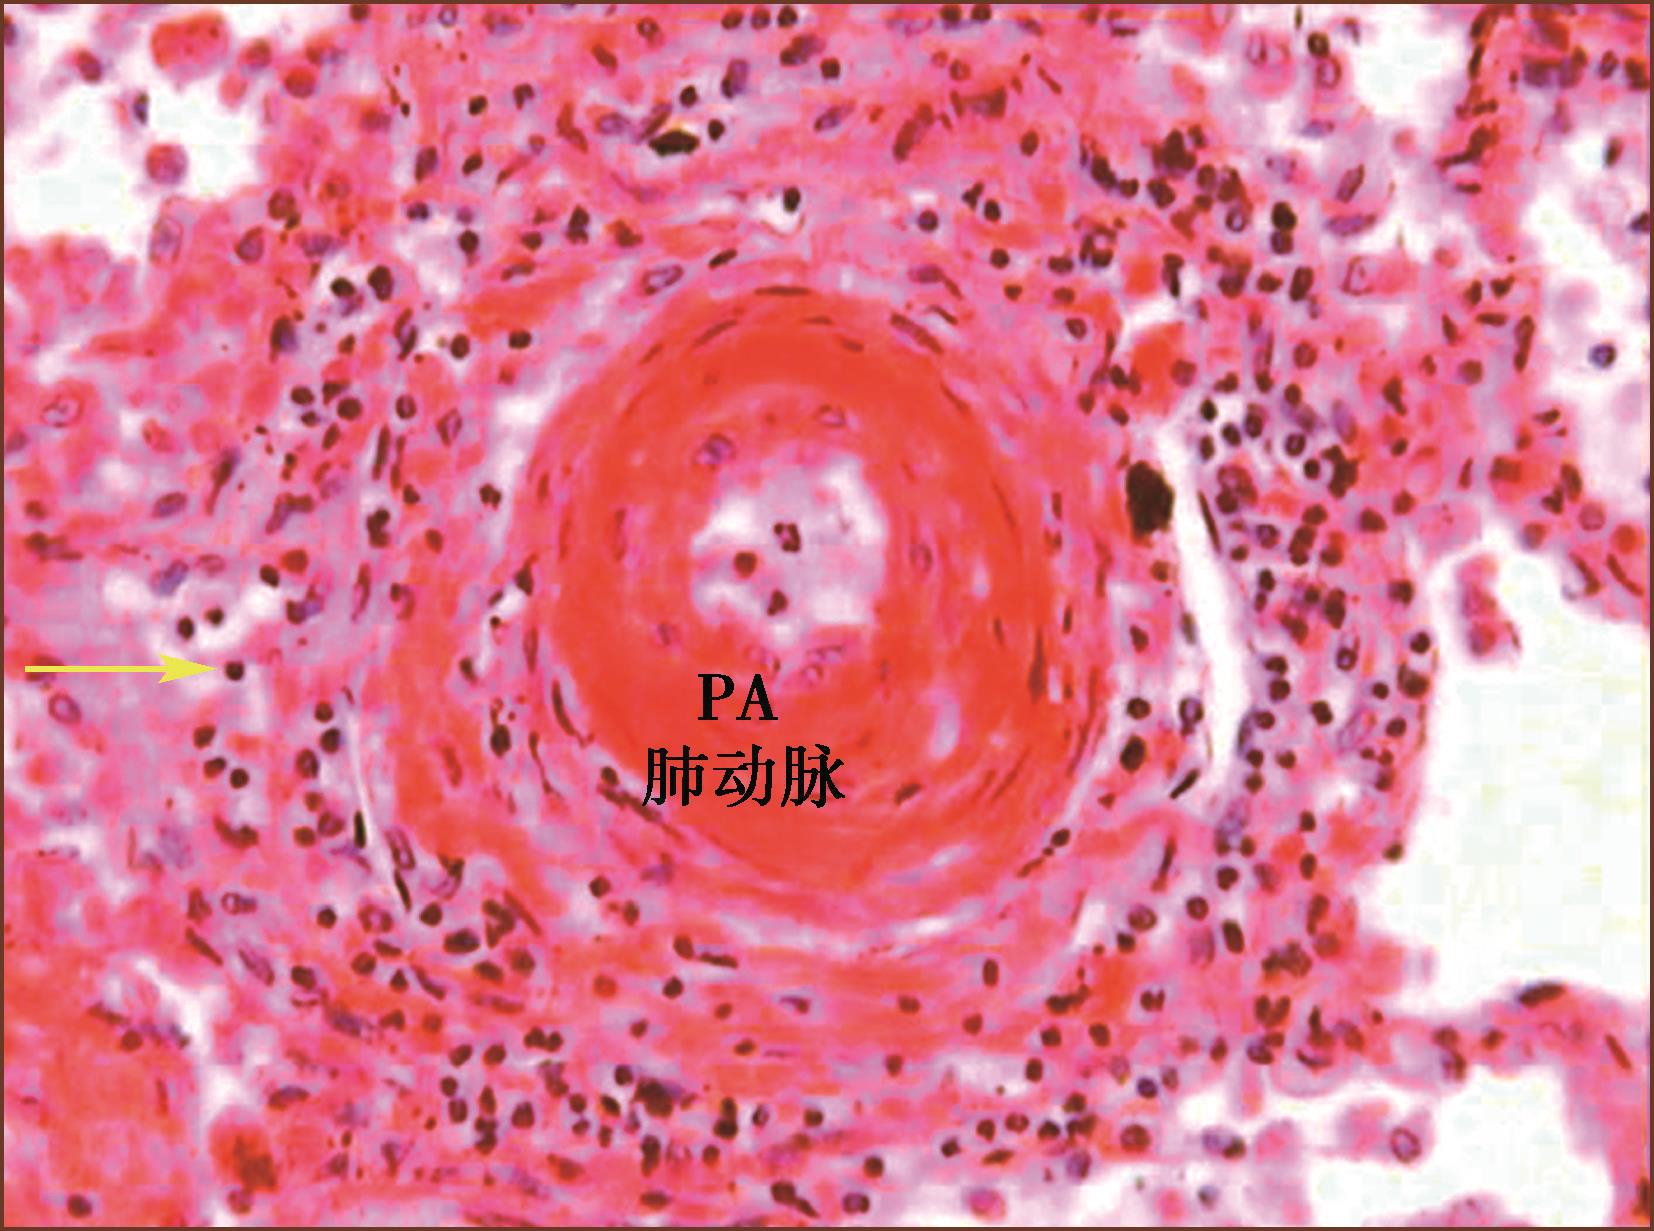

3.丛源性肺动脉病

在大多数严重的PAH,肌型肺动脉和肺微细动脉可发生纤维素样坏死(图3-1-10,图3-1-11)。坏死通常是节段性的,可发展成为动脉瘤样破裂,伴发间质或肺泡腔内出血,最终含铁血黄素沉积。局部修复性的重建血管瘤样的结构就是丛状病变(plexiform)。丛状病变是Ⅳ级肺动脉高压的标志。

丛状病变组织学显示由无规律生长的内皮细胞团(丛)状增生(有作者认为是肿瘤性内皮细胞增生)(图3-1-12,图3-1-13)。丛状病变组成成分有新生内皮细胞团(丛),混杂有肌纤维母细胞、平滑肌细胞和结缔组织基质,形成灶性薄壁的多个毛细血管裂隙。丛状病变的内皮细胞可被血管内皮生长因子(VEGF)和它的受体标记;用α-SM-Actin可以标记丛状病变内的肌纤维母细胞。有的作者形容丛状病变为血管球样生长。有时,丛状病变的管腔宽大,病变类似动静脉畸形。如果管腔内含有纤维素,要与机化血栓进行鉴别。在临床PAH中,丛状病变在肺活检组织中不易见到。在重症PAH一张组织切片上能见到一两处丛状病变,因此至少应该检查10个肺组织块,才能够除外丛状病变。有研究报道,特发性肺动脉高压的丛状病变为单克隆来源;反之在继发性肺动脉高压的丛状病变是多克隆来源。

图3-1-12 IPAH患者的肺小动脉的丛状病变(HE,中倍放大)

图3-1-13 先天性心脏病患者的肺小动脉的丛状病变(HE,中倍放大)

丛状病变可见在肺小动脉腔内(见图3-1-5)、好发于血管分叉处;也可侵入血管向肺小动脉外形成管壁外丛状病变(见图3-1-13);在丛状病变内还可见纤维素新血栓和血小板积累(图3-1-14)。丛状病变在PAH的发生率变异很大,有报告累及肺动脉分支的20%~60%。

图3-1-14 来自IPAH患者的肺小动脉丛状病变,多个厚薄不一、形状多样的小血管球状及丛状增生,即丛状病变,周围有组织坏死及大量淋巴细胞浸润,为坏死性动脉炎(HE,中倍放大),F:丛状病变